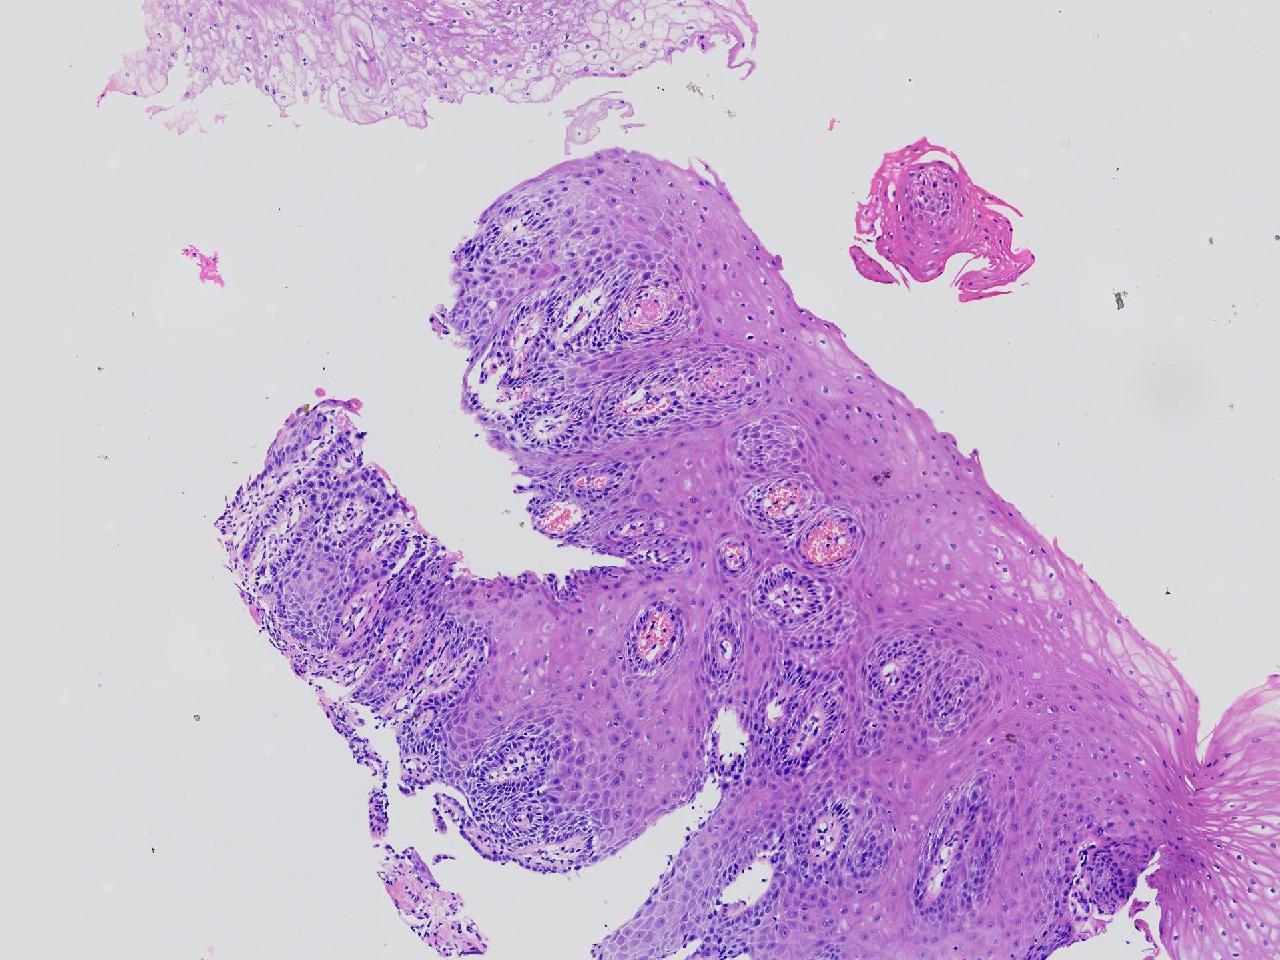

男,62岁,贲门口齿状线上见条状糜烂,活检1块,质软。

贲门口活检

灰白色不整形软组织1块,直径0.2厘米。

图1

鳞皮乳头状增生伴慢性炎。